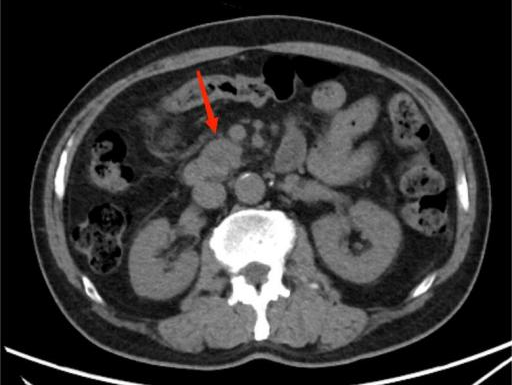

图3A

图3B

典型病例3:

女,62岁,无明显诱因出现腹痛,为左上腹痛,呈阵发性绞痛,程度剧烈。图A:平扫CT示胰尾部团块状稍低密度影(红箭头),与脾门分界不清;脾脏受侵,实质内见多发低密度影(黄箭头)。图B:增强扫描示胰尾部肿块呈轻度强化,脾脏多发低密度影呈轻度强化。